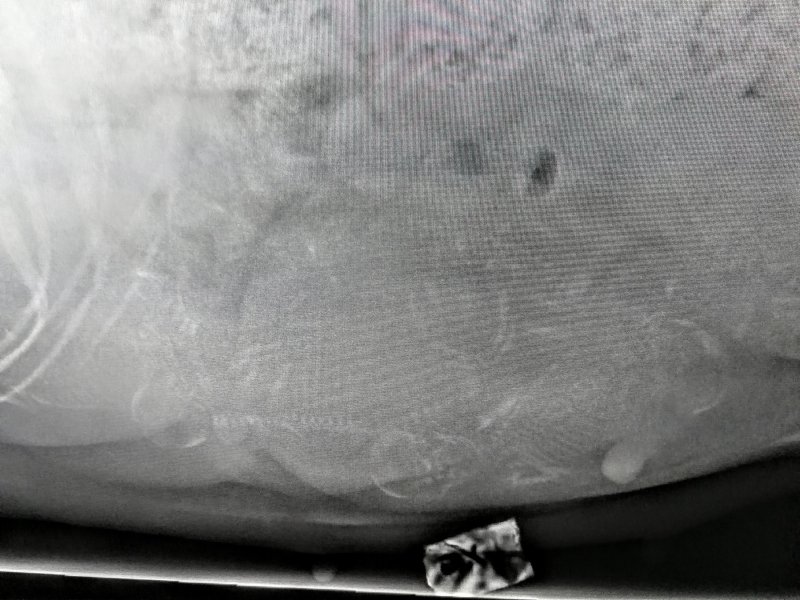

Ester skötte sig utmärkt under röntgen idag på morgonen. Tyvärr visade det sig att vi var lite för tidigt ute vilket gjorde att resultatet inte blev så tydligt som vi önskade. Vi kommer därför att göra en ny röntgen nästa torsdag vid 08.30 då vi hoppas på klara besked. Men visst är det valpar därinne. Frågan är bara hur många? Inget är som väntans tider. Men vad det är svårt att vänta!